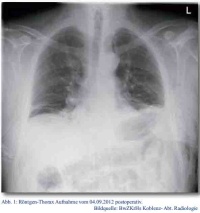

Auf Grund der ausgeprägten Vaskularisation und unklaren Dignität des Tumors entschieden wir uns daher für eine laparoskopische, onkologische Sigma-Resektion. Intraoperativ zeigten sich mehrere große Gefäßstrukturen, die in Richtung des tumortragenden Darmabschnittes zogen. Sie wurden einzeln frei präpariert und nach Clip-Ligatur durchtrennt. Der Tumor konnte, zusammen mit dem Colon Sigmoideum, in toto geborgen werden (siehe Abbildung 1).